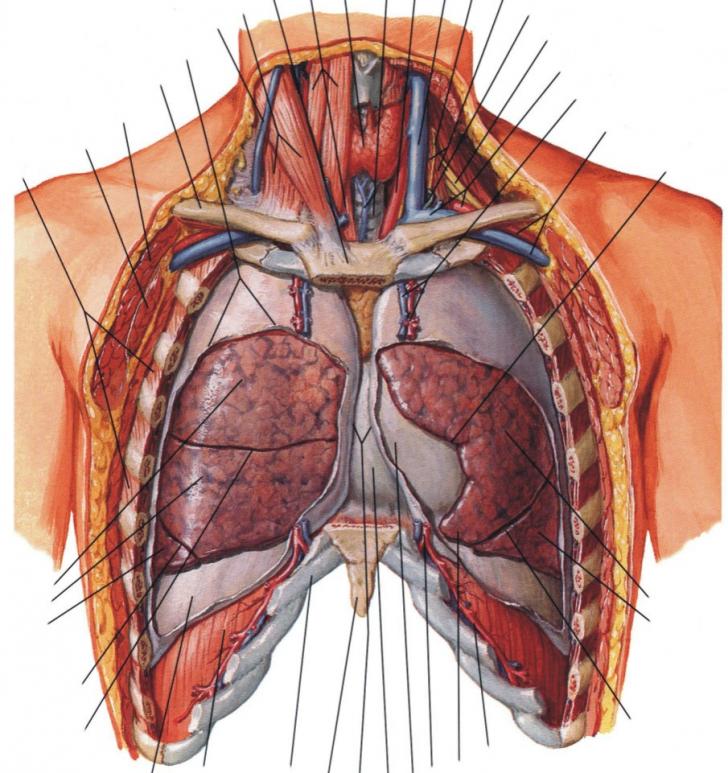

PATOLOGIE TORACICA - TRAUMATISME TORACICE

PATOLOGIE TORACICA I. SCURT RAPEL DE ANATOMIE TORACICA Trunchiul este alcatuit din torace, abdomen si pelvis. Toracele, partea superioara a trunchiului, este alcatuit dintr-un schelet (osteotorax) &#Citeste tot ... 8888 cuvinte

Dimensiune mare

+ cu imagini |